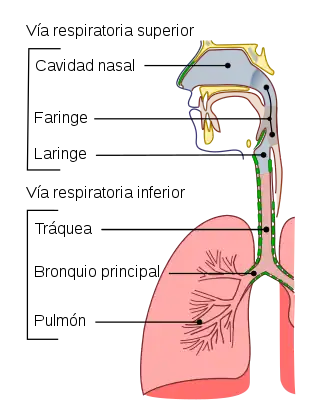

La mayor parte de los animales disponen de sistemas respiratorios que tiene la función de intercambiar gases entre sus células y el ambiente que los rodea, su estructura y función es muy variable dependiendo del tipo de organismo. El aparato respiratorio o sistema respiratorio es el conjunto de órganos que sirven para intercambiar gases con el medio ambiente. En los vertebrados terrestres está formado por las vías aéreas y los pulmones. A través de las vías aéreas, el aire circula en dirección a los pulmones, y en estos órganos la sangre capta el oxígeno y se desprende del dióxido de carbono.[1][2]

El órgano principal del aparato respiratorio humano y de los animales mamíferos es el pulmón. En los alveolos pulmonares se produce mediante difusión pasiva el proceso de intercambio gaseoso, gracias al cual la sangre capta el oxígeno atmosférico y elimina el dióxido de carbono (CO2) producto de desecho del metabolismo.[3] El aparato respiratorio humano está constituido por las fosas nasales, boca, faringe, laringe, tráquea y pulmones. Los pulmones constan de bronquios, bronquiolos y alveolos pulmonares.[4]

El aparato respiratorio humano consta de los siguientes elementos:

- Fosas nasales: Son dos amplias cavidades cuya función es permitir la entrada y salida del aire, el cual se humedece, filtra y calienta a través de unas estructuras llamadas cornetes.

- Faringe: Estructura con forma de tubo situada en el cuello y revestido de membrana mucosa; conecta la cavidad bucal y las fosas nasales con el esófago y la laringe.

- Laringe: Es un conducto que permite el paso del aire desde la faringe hacia la tráquea y los pulmones. En la laringe se encuentran las cuerdas vocales que dejan entre sí un espacio llamado glotis.

- Tráquea: Es un conducto en forma de tubo que tiene la función de hacer posible el paso del aire entre la laringe y los bronquios. Su pared está reforzada por un conjunto de cartílagos con forma de C que dificultan que la vía se colapse por compresión externa sobre el cuello.[6]

- Pulmones: Órganos cuya función es realizar el intercambio gaseoso con la sangre. Dentro de cada pulmón, el árbol bronquial se divide progresivamente dando ramificaciones cada vez más pequeñas. La tráquea da origen a los dos bronquios principales que se dividen en bronquios secundarios o lobulares. Cada bronquio lobular se divide en bronquios terciarios o segmentarios que se dividen en bronquiolos. El bronquiolo continúa el proceso de ramificación y da origen al bronquiolo terminal de donde parten los bronquiolos respiratorio que es donde se encuentran los sacos alveolares.